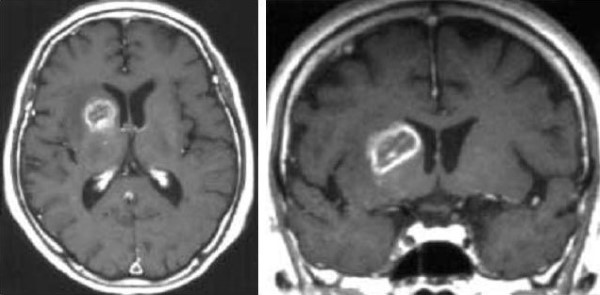

Hình 4 a/b. Glioblastoma? Bệnh nhân nữ 75 tuổi bị rung nhĩ được nhập viện, không có triệu chứng thần kinh. (Chẩn đoán cuối cùng: nhồi máu giai đoạn bán cấp ở vùng phân bố động mạch vân ngoài phải). Các ảnh SE T1-W (460/12) cắt ngang (a) và đứng ngang (b) cho thấy tổn thương ngấm thuốc hình vòng không đều ở phần trước nhân nền phải.

a: Tổn thương liên quan đến cả cánh tay trước của bao trong phải.

b: Tổn thương ngấm thuốc được vạch rõ theo sự phân bố của động mạch vân ngoài trên ảnh cắt đứng ngang. Không điều trị, tổn thương co nhỏ tự phát sau vài tuần (không trình bày hình ảnh theo dõi).